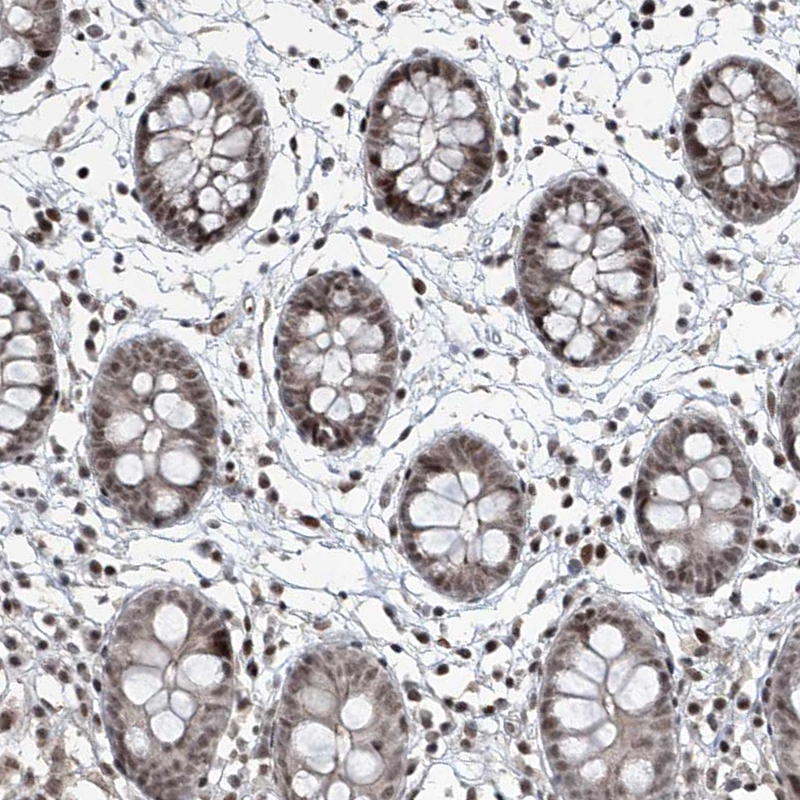

Immunohistochemical staining of human colon shows strong nuclear positivity in glandular cells.